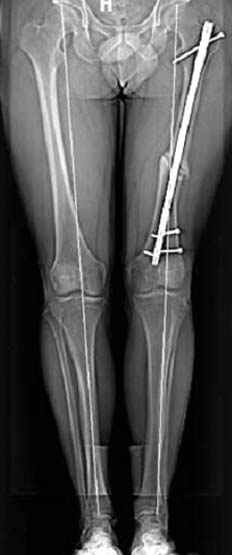

Несколько снимков из моей коллекции, чтобы разьяснить, почему мы до сих пор делаем различные варианты остеотомии.

На рисунке N1 предоперационный план лечения ложного сустава шейки бедра- линия ложного сустава, угол и направление введения импланта, клиновидная остеотомия в градусах и миллиметрах, второй снимок после коррекции, расчет, на сколько удлиняется конечность и размеры импланта;

N3 рисунок окончательный снимок, после операции моя рентгенограмма должен выглядеть примерно как эта картина. На N4 снимке клин перед удалением; N5 послеоперации 3 нед.; N6 окончательная рентгенограмма.

варус при проксимальном отделе 95 градусной пластиной.

Интересно бы посмотреть рентгенограмму таза (оба сустава) а также рентгенгорамму с захватом коленных суставов (по Dror Paley).